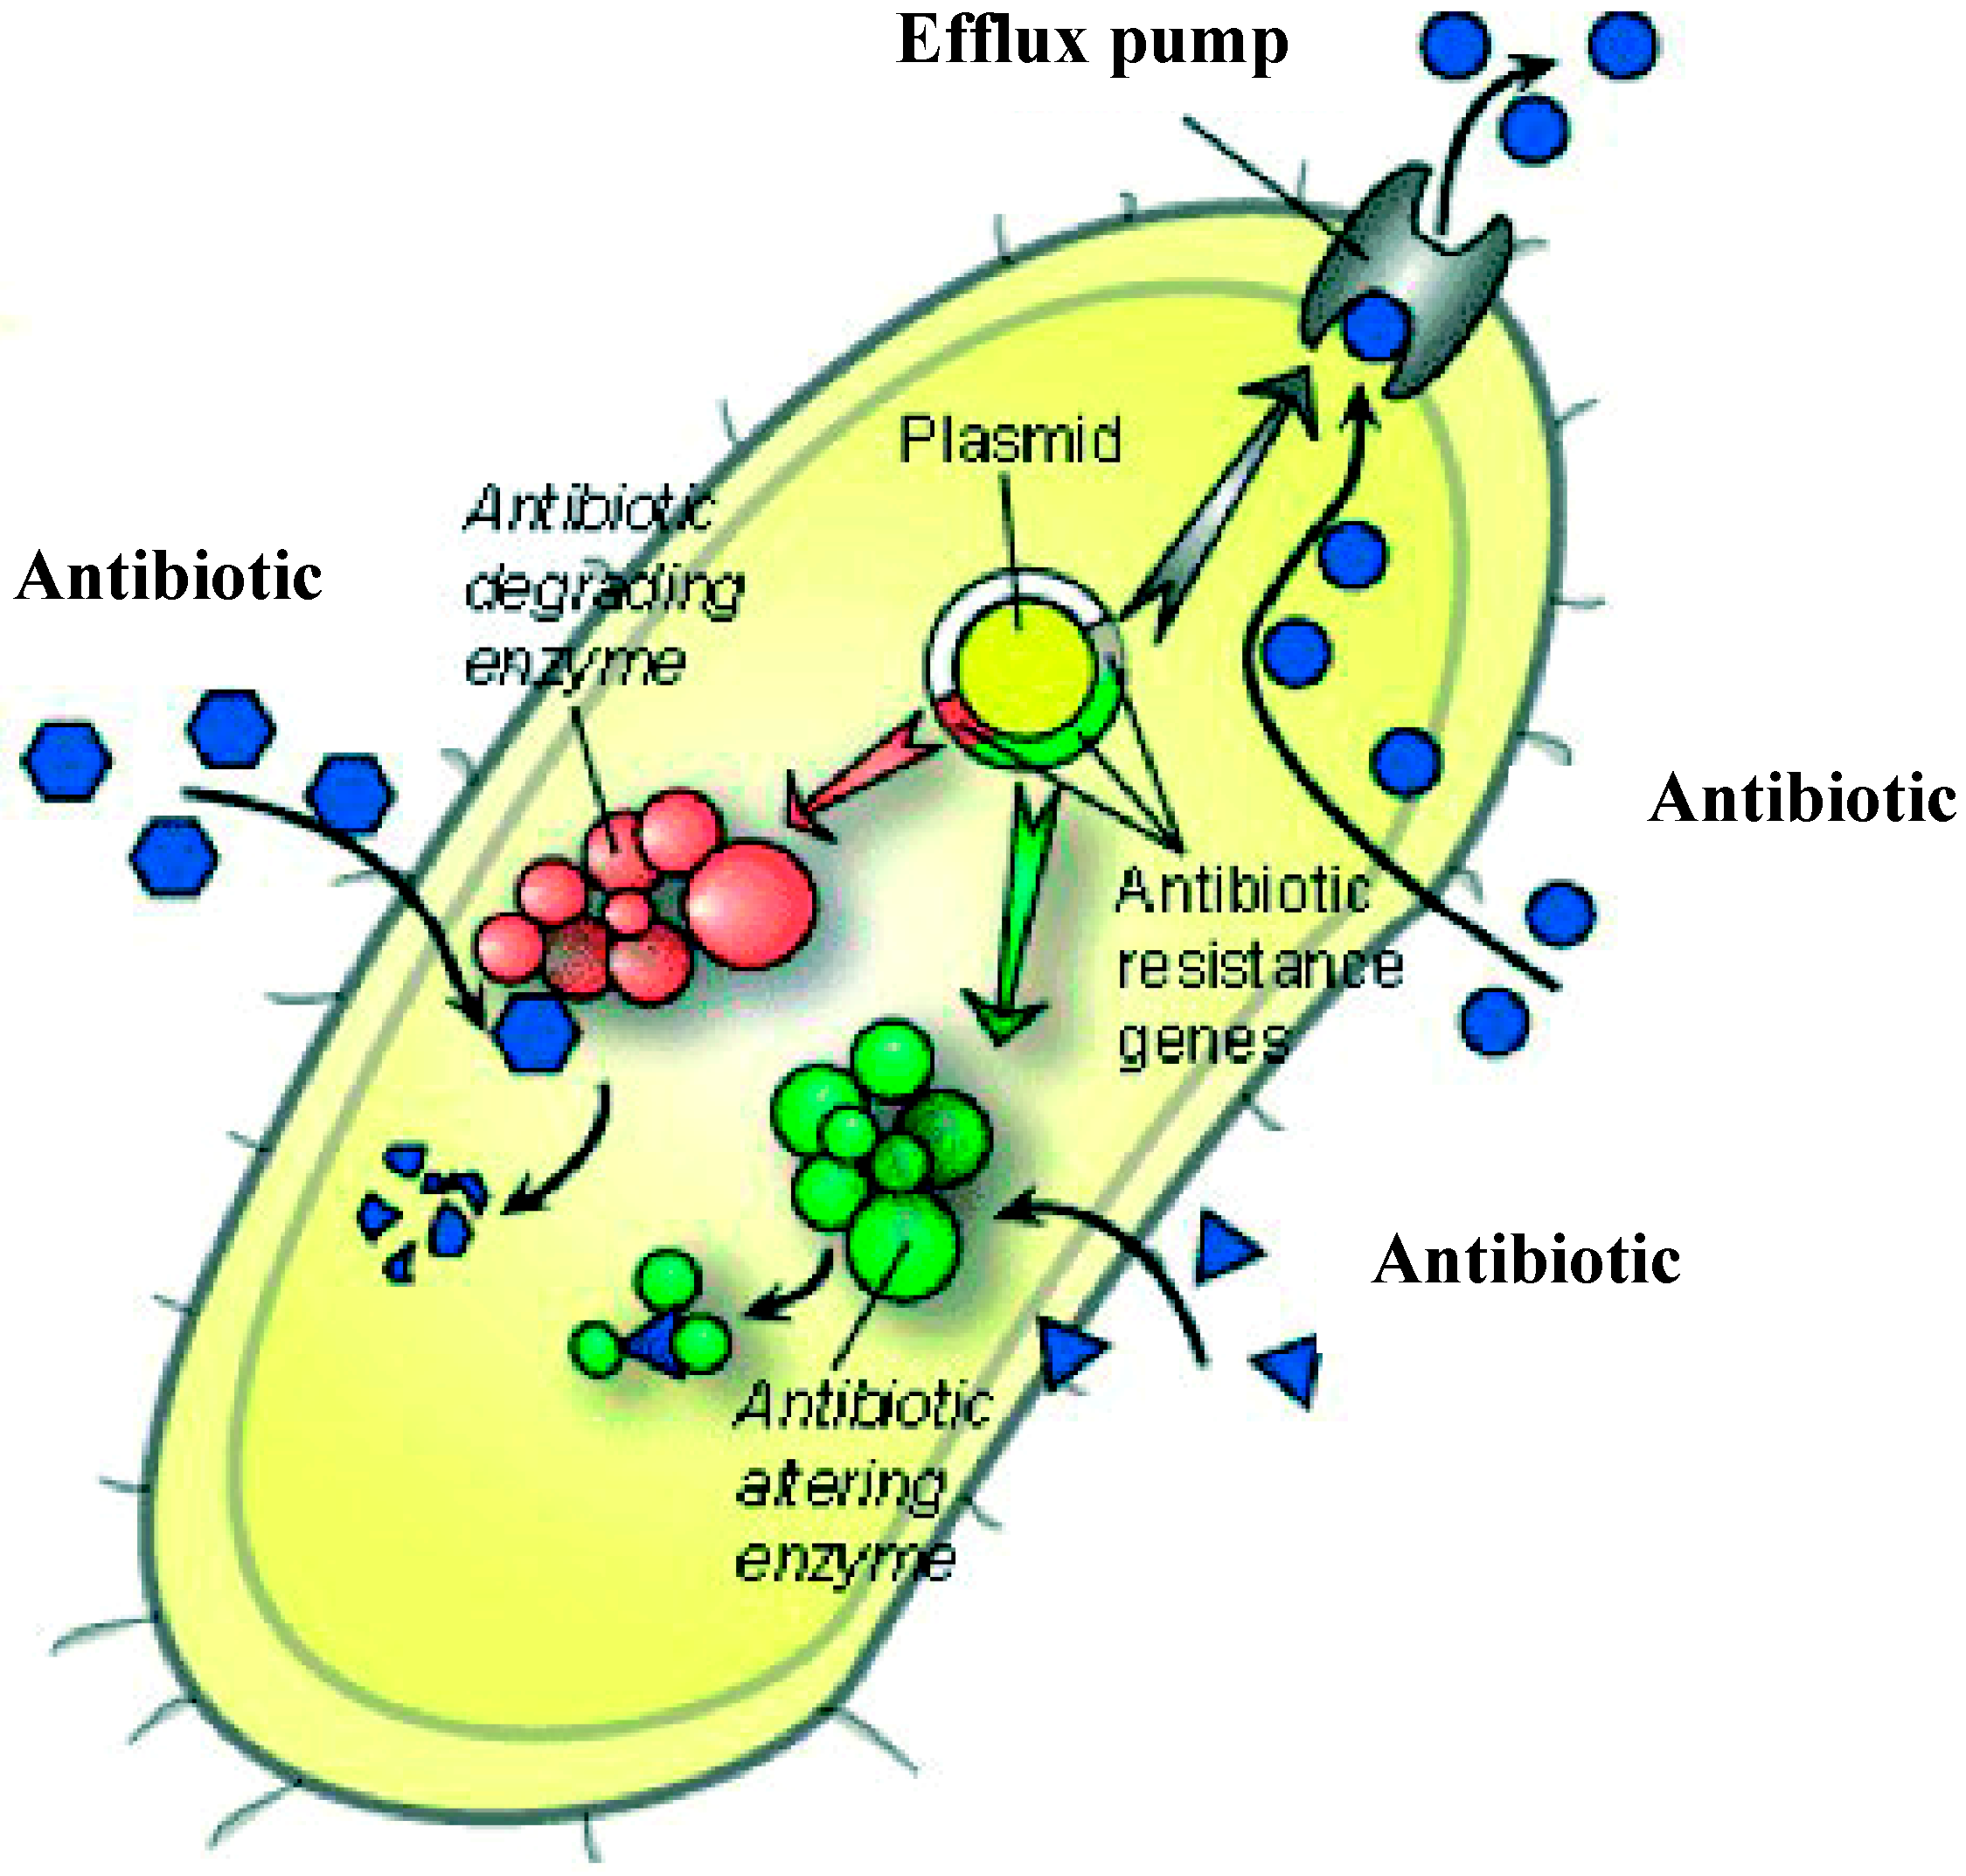

Механизмы действия антимикотиков: схемы и изображения